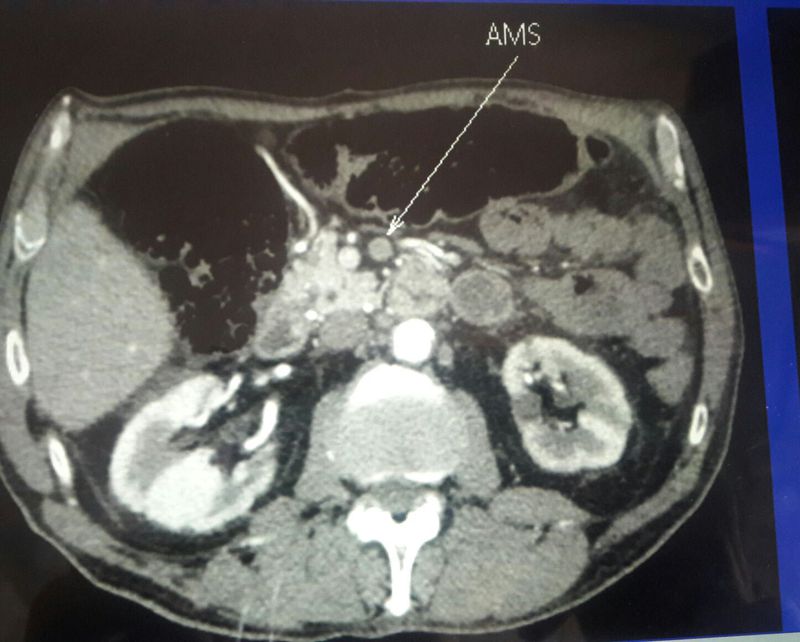

76-year-old patient with complete arrhythmia with untreated atrial fibrillation acute umbilical abdominal pain since 24 hours diffuse abdominal defense free hernias TA: 95/65 - irregular pulse: 90 / min - Hb: 14g / l - serum creatinine: 150mmol / l RA: 18 - blood lactates: 5mmol / What's your diagnosis? And why?